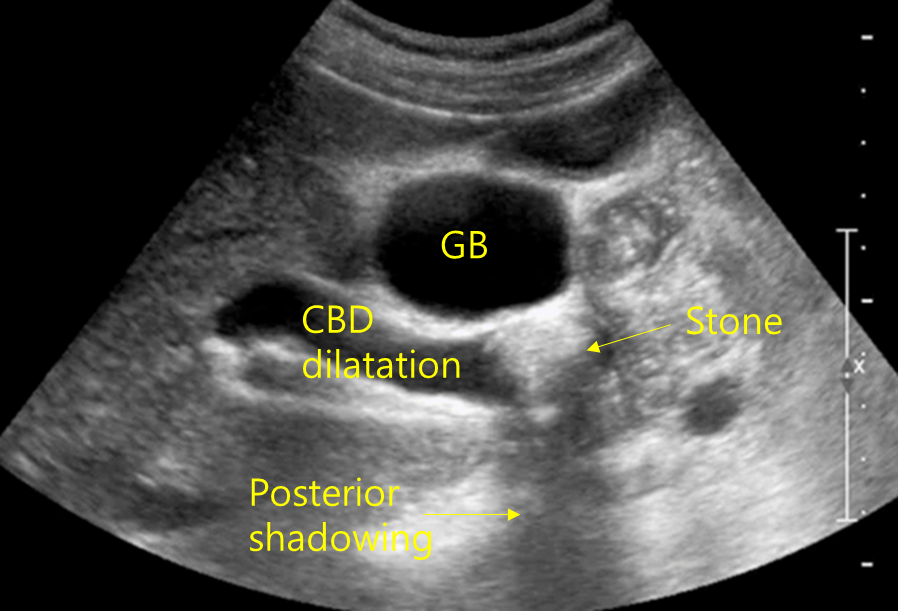

Img | US: CBD stone with posterior acoustic shadowing, proximal CBD dilatation |

Biliary colic pain, 발열, 고빌리루빈혈증이 있으며 US상 CBD stone이 보이므로 온쓸개관돌로 진단할 수 있다.

• 이는 US상 CBD 내부에 posterior acoustic shadowing이 보이는 hyperechoic stone으로부터 확진할 수 있다.

• 이자돌: 본 증례의 경우 amylase/lipase 상승이 없으며, US에서 관찰되는 부분은 pancreatic duct가 아닌 CBD이다(위쪽에 담낭, 왼쪽에 간이 보이므로 CBD임을 알 수 있다).